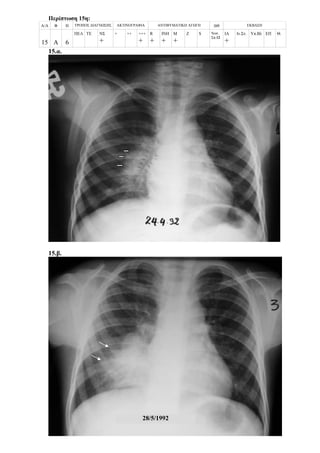

Περίπτωση 15η:

Α/Α Φ Η ΤΡΟΠΟΣ ΔΙΑΓΝΩΣΗΣ ΑΚΤΙΝΟΓΡΑΦΙΑ ΑΝΤΙΦΥΜΑΤΙΚΗ ΑΓΩΓΗ ΔΘ ΕΚΒΑΣΗ

15 Α 6

ΠΕΛ ΤΕ ΝΣ

+

+ ++ +++

R

ΙΝΗ

Μ

Z S Νοσ.

Σπ.12

ΙΑ

Ιν.Στ. Υπ.Βλ ΕΠ Θ.

15.α.

15.β.

28/5/1992

15.γ.

15.δ.

15.ε.